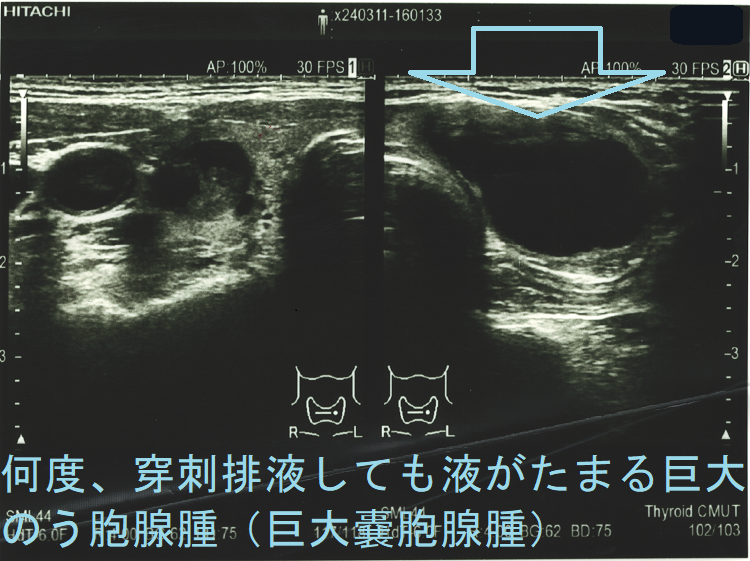

頻回に穿刺排液しても液がたまる巨大のう胞腺腫(巨大嚢胞腺腫)は、良性腫瘍(のう胞型濾胞腺腫:嚢胞型濾胞腺腫)であっても手術適応になります。単に、のう胞(嚢胞)と呼ばれる事も多いですが、甲状腺組織の破壊・変性によるのう胞変性(嚢胞変性)でなく、れっきとした腫瘍です。

岩手県立中央病院の報告;97 x 71 x 60 mmの巨大な甲状腺のう胞腺腫(甲状腺嚢胞腺腫)で、排液後1週間以内に液が再貯留し始めたため、甲状腺半葉切除したそです。病理標本では、のう胞周囲は炎症が強く、炎症性浸出液の可能性が考えられます。(第57回 日本甲状腺学会 P2-070 巨大な甲状腺嚢胞により経口摂取困難となった一例)

ケース⓪ 巨大のう胞腺腫(巨大嚢胞腺腫) 気管圧排

ケース① 巨大のう胞腺腫(巨大嚢胞腺腫) 7 cm以上

ケース② 巨大過ぎる甲状腺のう胞腺腫(甲状腺嚢胞腺腫) 8 cm以上